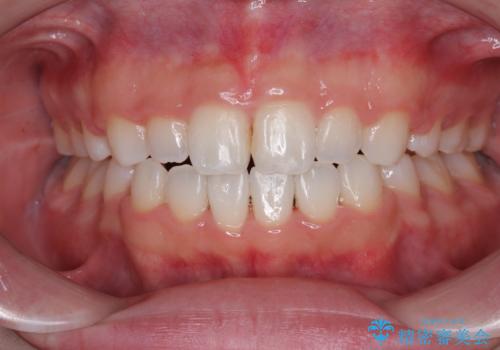

【審美装置】前歯で噛めない!抜歯しないで治したい

MARPEで非抜歯矯正|オープンバイトと八重歯を改善